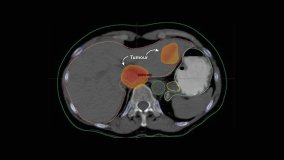

Killing More Cancer Cells than Ever Before: A New Era in Radiotherapy

Radiation revolutionized medicine when it was first used to treat cancer in 1901. Its use, however, has only been able to evolve as far as technical innovation has allowed.